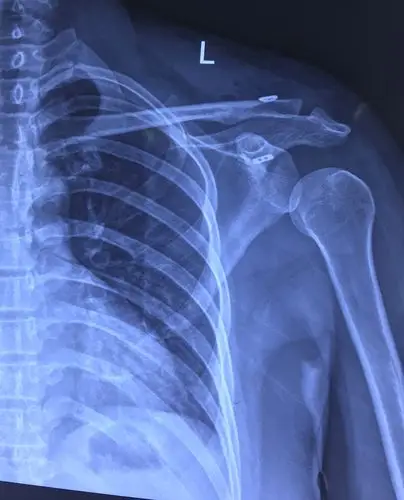

国际蒙医院骨伤科今日成功完成一例肩锁关节脱位肩关节镜喙锁韧带重建

前屈及后伸运动受限;肩锁关节处可摸到凹陷,锁骨远端上翘明显;余肢